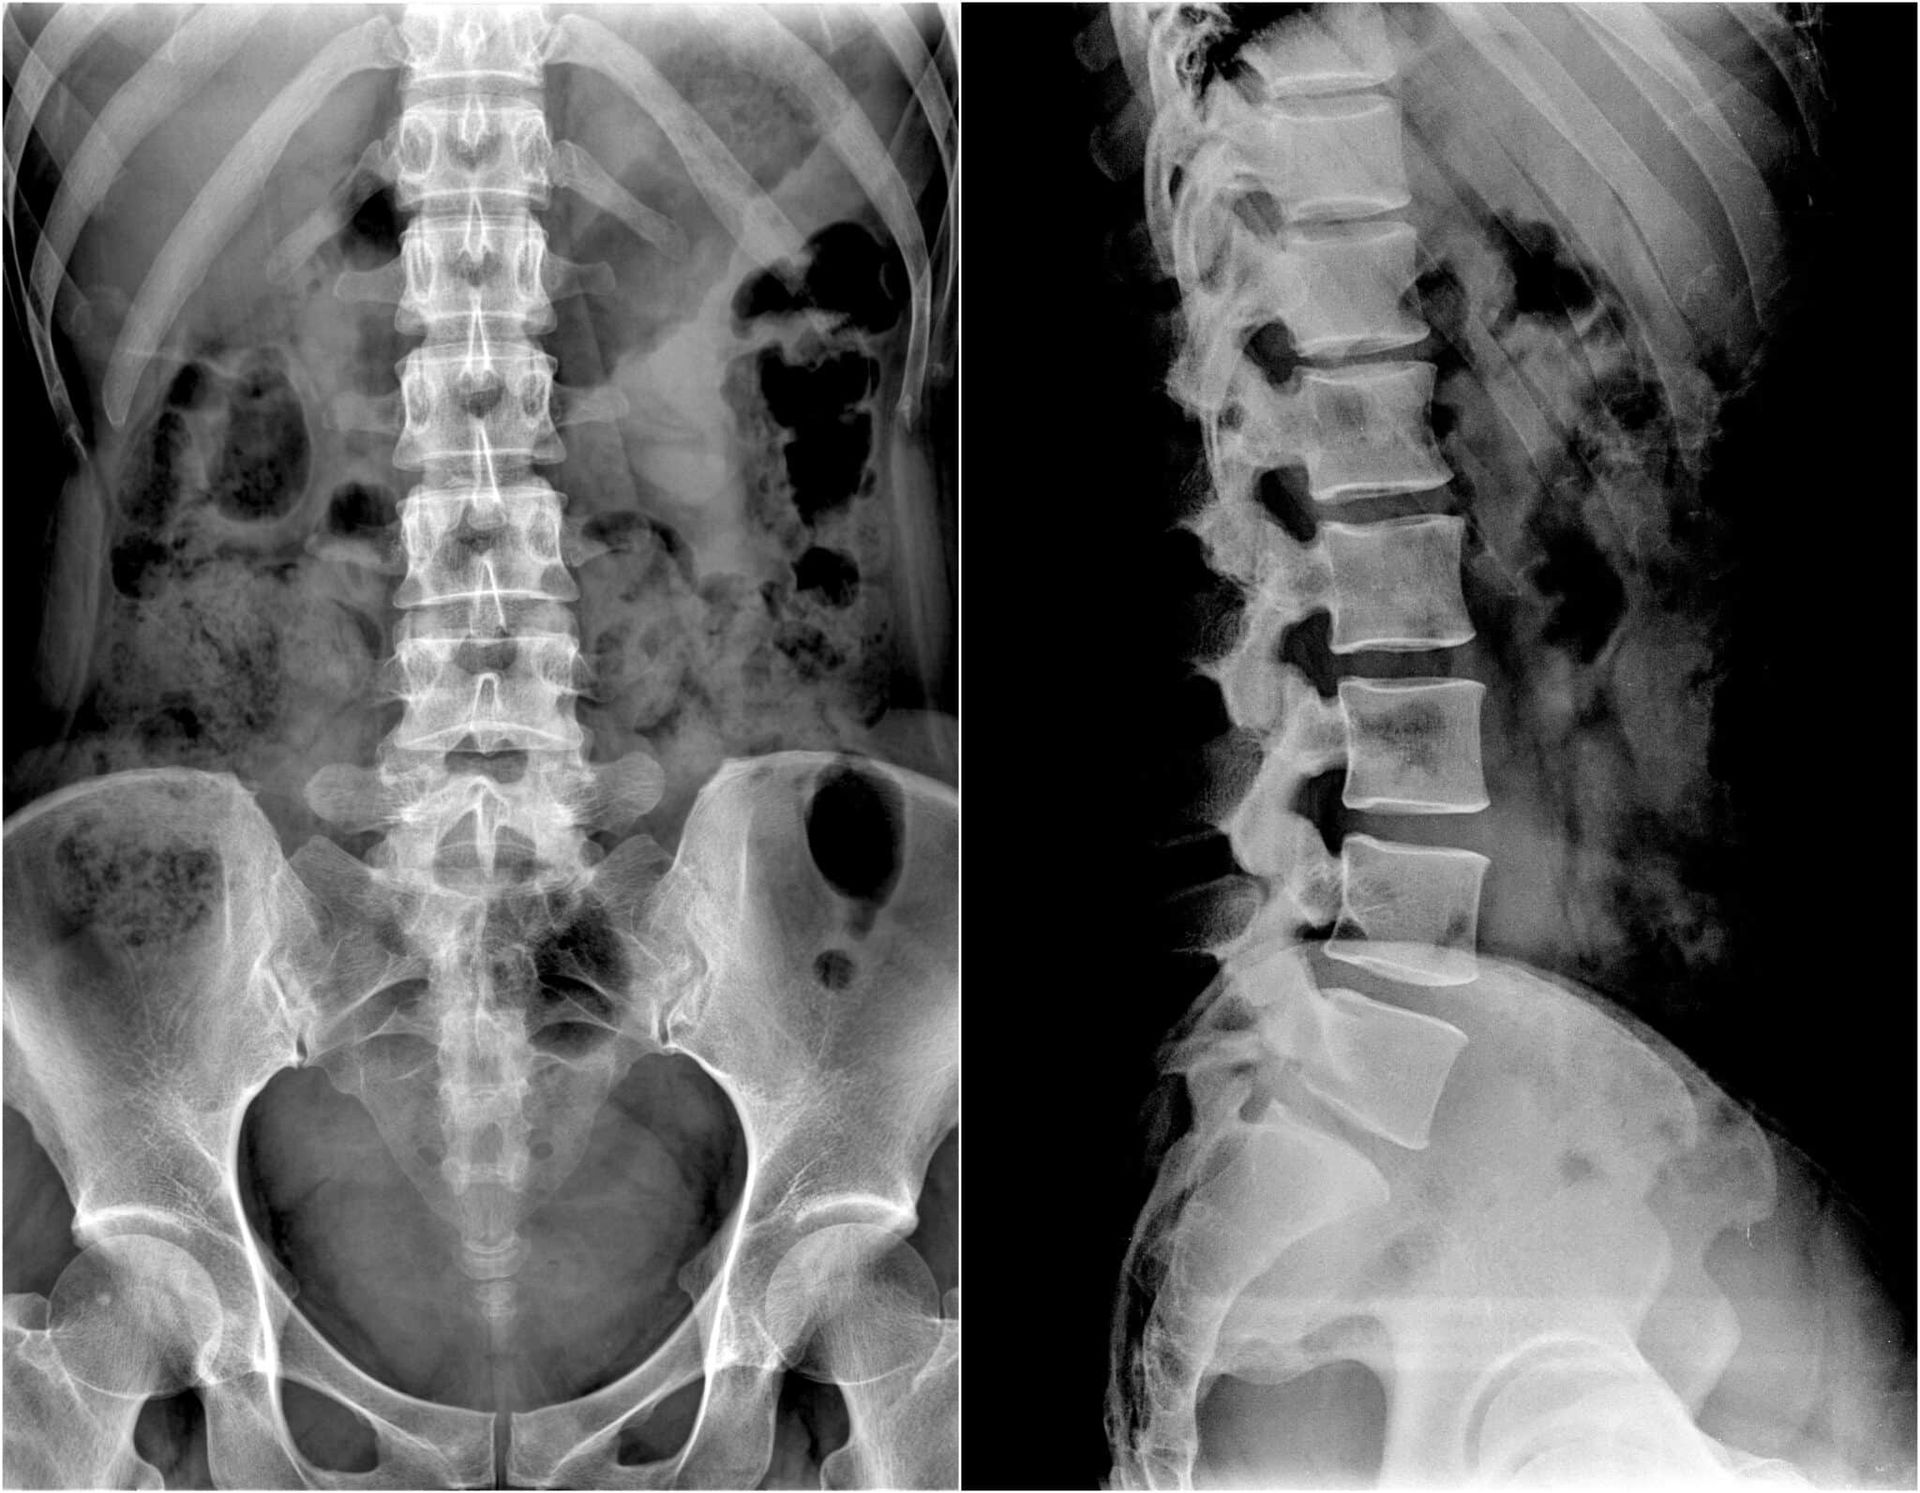

Diagnostic Tests (If Necessary)

Once the physical examination is done, there may be a need for diagnostic tests. These include MRIs, X-rays, or other imaging. This brings forth a clear picture of your spine and joints. If there is anything that requires further deliberation, the chiropractor will pinpoint issues and then suggest the ideal treatment for it.